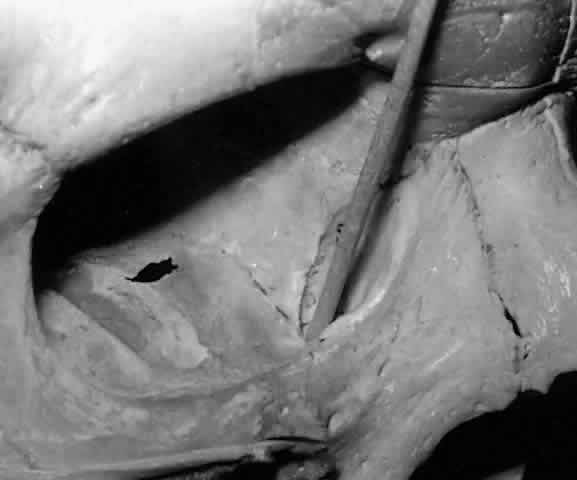

Lining the lacrimal fossa and surrounding the lacrimal sac is a dense, fibrous membrane that Jones termed the lacrimal fascia.2 The upper and lower canaliculi narrow as they course medially to traverse the lacrimal fascia individually before they join, in the majority of cases, to form the common canaliculus (Fig. 19). The common canaliculus is located 2 to 3 mm posterior to the central portion of the medial canthal tendon. Histologically, the common canaliculus represents a diverticulum of the lacrimal sac and, if enlarged, is known as the sinus of Maier. The point of common canalicular entrance into the lacrimal sac is slightly above the midpoint of the sac on its lateral wall. In approximately 10% of cases, the upper and lower canaliculi can be found entering the lacrimal sac through separate openings, without the presence of a common canaliculus.20

Fig. 19. The upper and lower canaliculus, in the majority of cases, join to form the common canaliculus (pointer). The common canaliculus enters the lateral wall of the sac slightly above the midpoint of the sac.